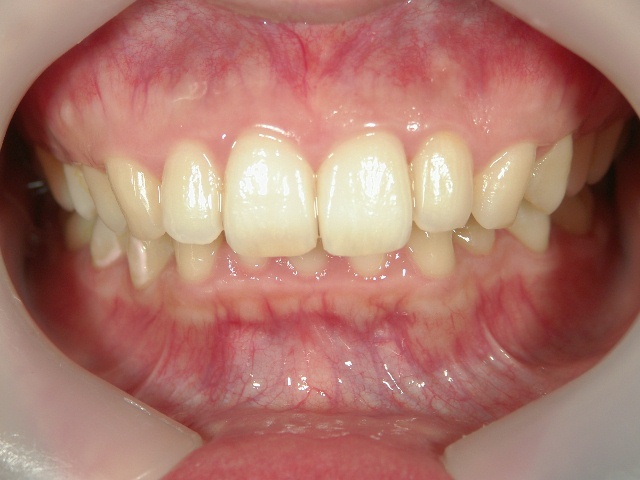

矯正歯科 治療後

矯正歯科 治療後 正面